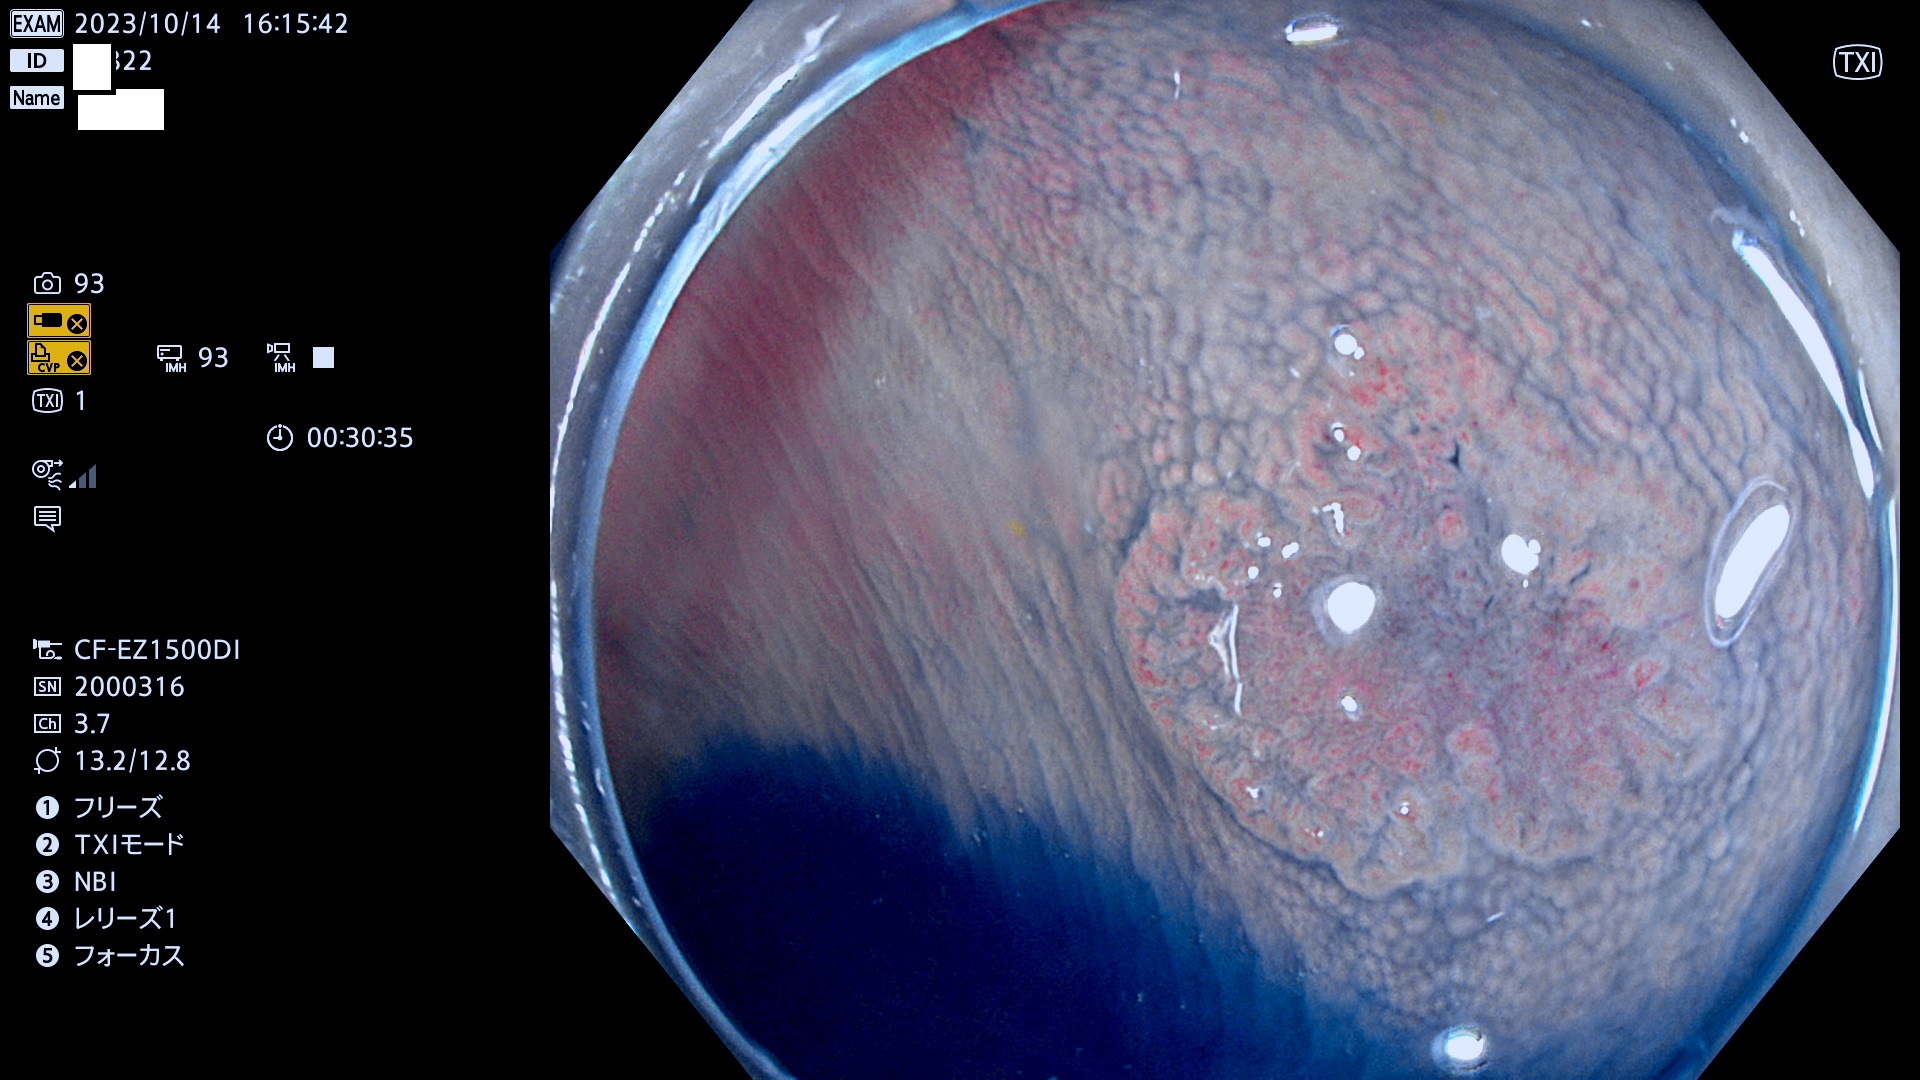

表面型腺腫(Flat Adenoma)の中で、完全に平坦な物をUb、陥凹している物をUcと呼びます。平坦隆起型(Ua)よりも、発見が難しく危険な病変です。このタイプは「内視鏡後・大腸癌の重要犯人」であり、この発見率は「腺腫発見率」よりも、重要な意味があります。

毎週の検査(木・金・土・日)に発見されたUb、Uc型・腺腫を、その週の日曜の夜にUPし1週間、提示します。

抽出の対象期間 2023年10月12日(木)〜10月15(日)の5日間(48件の検査)4件